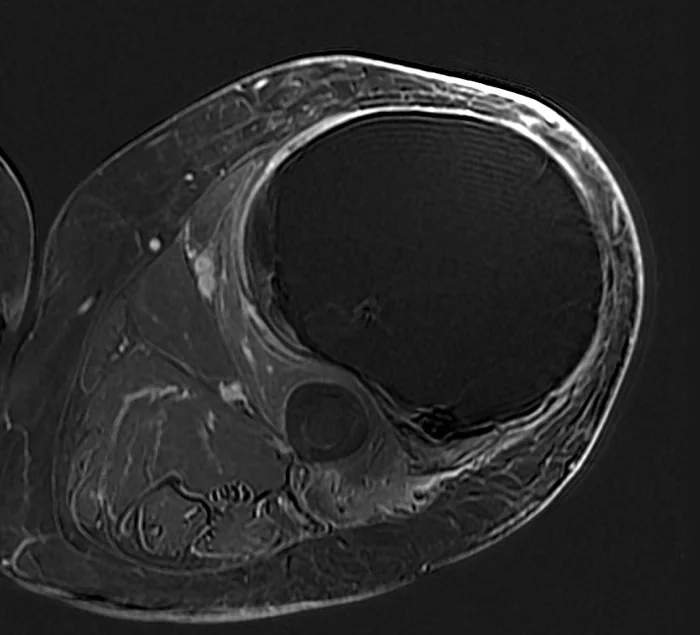

This 18 year old boy had pain in his knee that was not going away over a period of months. Eventually X-rays were done (first image on the left) which show the hallmark findings of osteosarcoma. As seen more closely on the second image, there is a mass adjacent the bone which is calcified. This is almost definitive for osteosarcoma. The last two are MRI images showing the tumor extending up and outside the femur. His tumor was localized to the femur (Stage IIb).